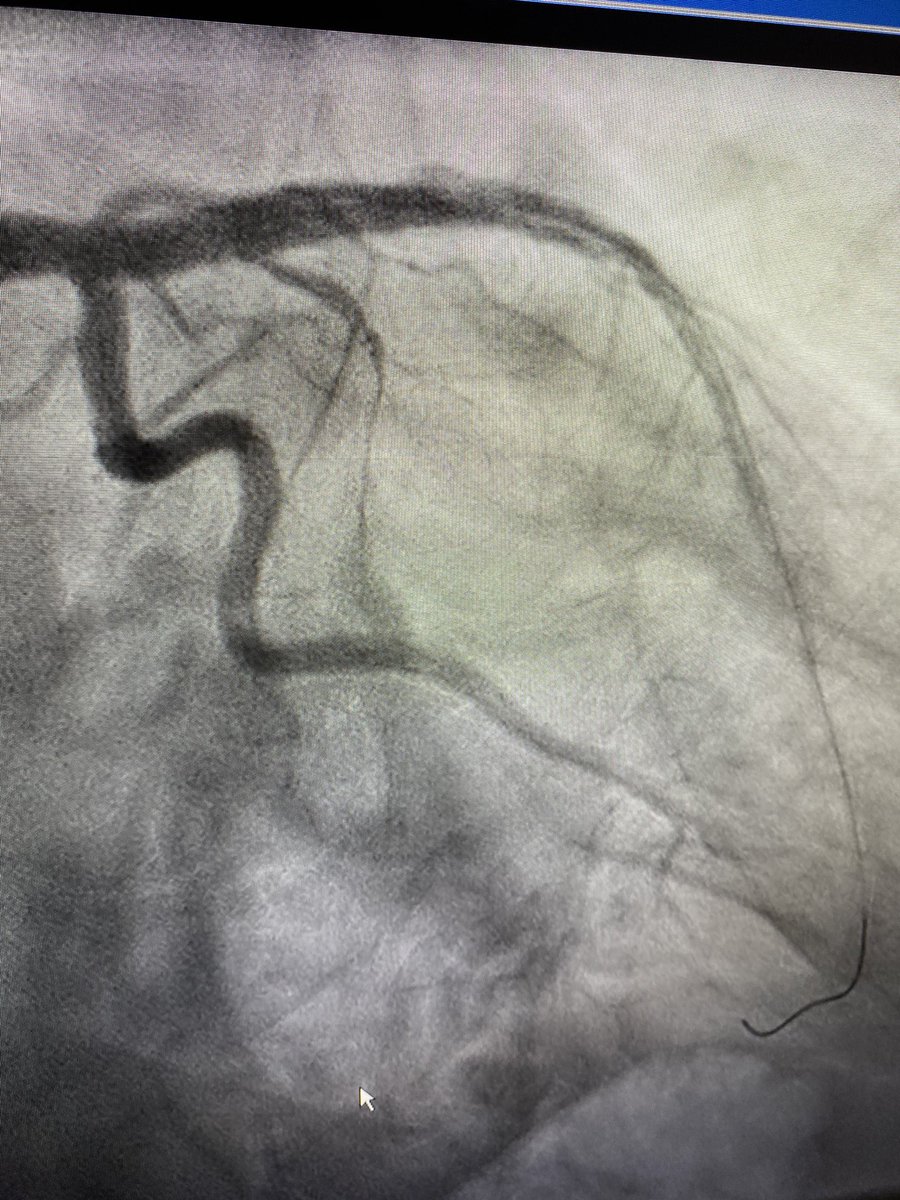

IVUS must be incorporated into you practice. 72 m with Recent LAD stent. Severe new denovo lesion at Prox stent edge. Stent placed 9 months prior.

Dropped new stent 4.5mm and postdilated old stent to 4.25mm. Post IVUS with excellent expansion and no more malapposition. Looks grossly oversized on post angio.